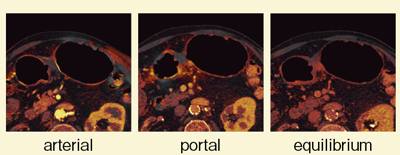

症例1は,胃角部V型胃がんである。胃角部小彎側のやや後壁寄りに,かなり深い潰瘍が認められた。DEで撮影したところ,逐次近似画像再構成法であるSAFIREを併用したcomposite imageにて,病変部が最も明瞭に描出された(図1)。ダイナミックCTを施行したところ,動脈相では80kVで粘膜が,門脈相では80kVで腫瘍が最も良好に濃染した(図2)。また,Liver VNCでiodine imageを評価したところ,50〜100%の画像で胃壁が最も良好に濃染しているが,腫瘍は濃染していなかった(図3)。さらに,SAFIREを用いたcomposite imageでは,特に平衡相で,どの部分に多く造影剤が流入しているかが理解しづらい(図4)。そこで,iodine imageを作成したところ,門脈相から平衡相にかけて,後壁部分がきわめて良好に濃染していることがわかった(図5)。これにより,後壁中心に線維化の強い胃がんと診断できた。本症例は潰瘍があるため,深達度診断が難しいが,胃壁外の血管の拡張も明瞭に認められ,進行がんの可能性があると思われる。

![]() 図2 症例1:ダイナミックCT(SAFIRE使用) |